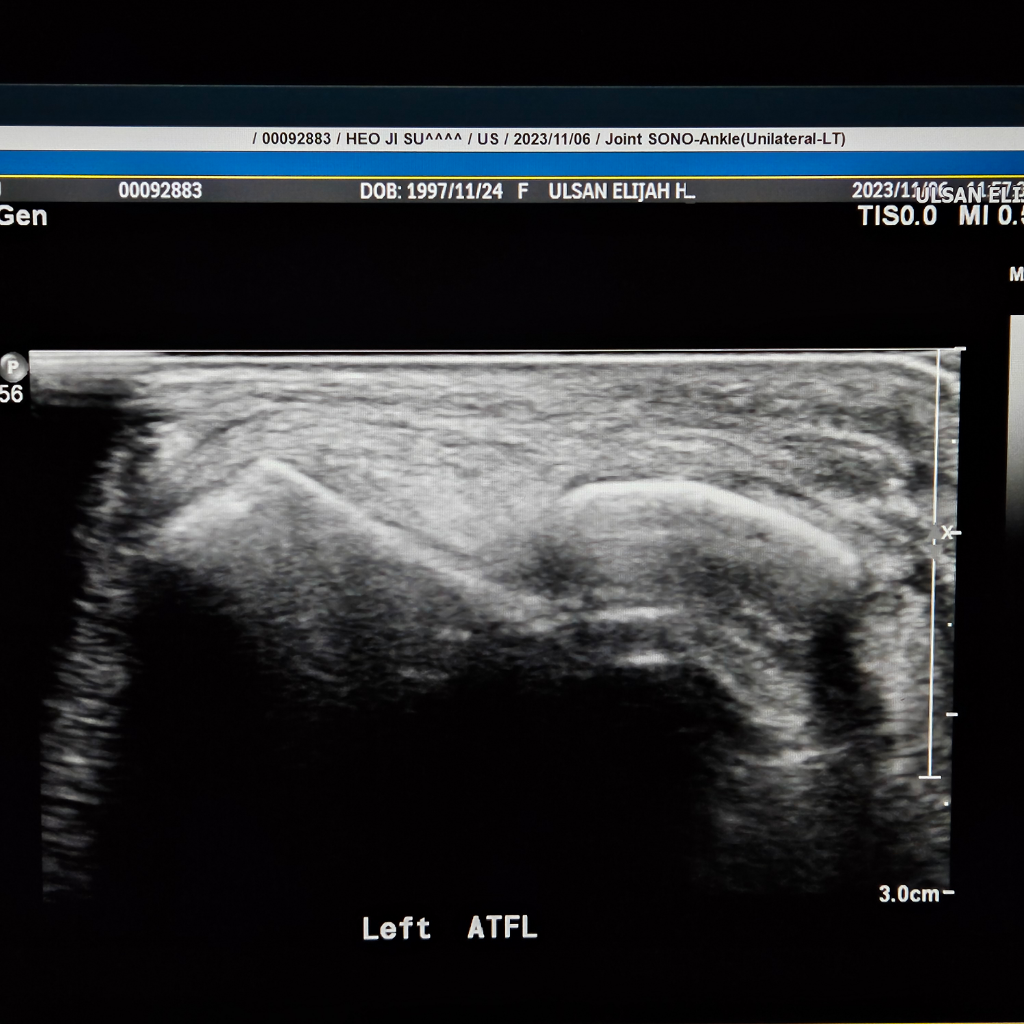

발을삐어서 병원을 갔는데 인대가 파열됬다는데 맞는지요?

발을 삐어서 병원을 갔는데 첨에 걸을때 넘아파서 못걸을정도 였습니다. 복숭아뼈 주위도 부워있었고

초음빠도 찍었습니다. 초음파에서 인대가 끈어졌다는데

끈어진게 맞나요? 첨에 수술 예기 하더니 아직 젊으니 반깁스 하고 일주일 두고보자고했습니다.

• 1번 째 사진

초음파는 실시간으로 발목을 움직여보면서 찍습니다.

검사자가 가장잘 판단을 내릴수 있습니다.

해당병원에 재문의해보세요.